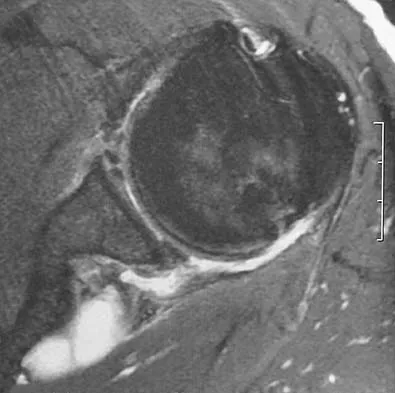

A 44-year-old recreational weight lifter reports chronic deep pain in his left shoulder that is aggravated by any pressing exercises. He also notes a painful catch in the shoulder occurring with rotational movements. Physical therapy and nonsteroidal anti-inflammatory drugs for 3 months have failed to provide relief. Examination reveals pain with O'Brien's test but no signs of instability. MRI scans are shown in Figures 4a and 4b. Treatment should now consist of

Explanation

The MRI scans show a large paralabral ganglion cyst in the spinoglenoid notch that communicates with an extensive tear of the glenoid labrum. Snyder and associates have classified superior labral tears into several subtypes that reflect the location and extent of the injury. Arthroscopic repair of the labral tear and aspiration of the ganglion cyst is the treatment of choice. Open excision of the cyst does not address the underlying problem of the labral tear. Snyder SJ, Karzel RP, Delpizzo W: SLAP lesions of the shoulder. Arthroscopy 1990;6:274-279. Piatt BE, Hawkins RJ, Fritz RC, et al: Clinical evaluation and treatment of spinoglenoid notch cysts. J Shoulder Elbow Surg 2002;11:600-604. McFarland EG, Kim TK, Savino RM: Clinical assessment of three common tests for superior labral anterior-posterior lesions. Am J Sports Med 2002;30:810-815.